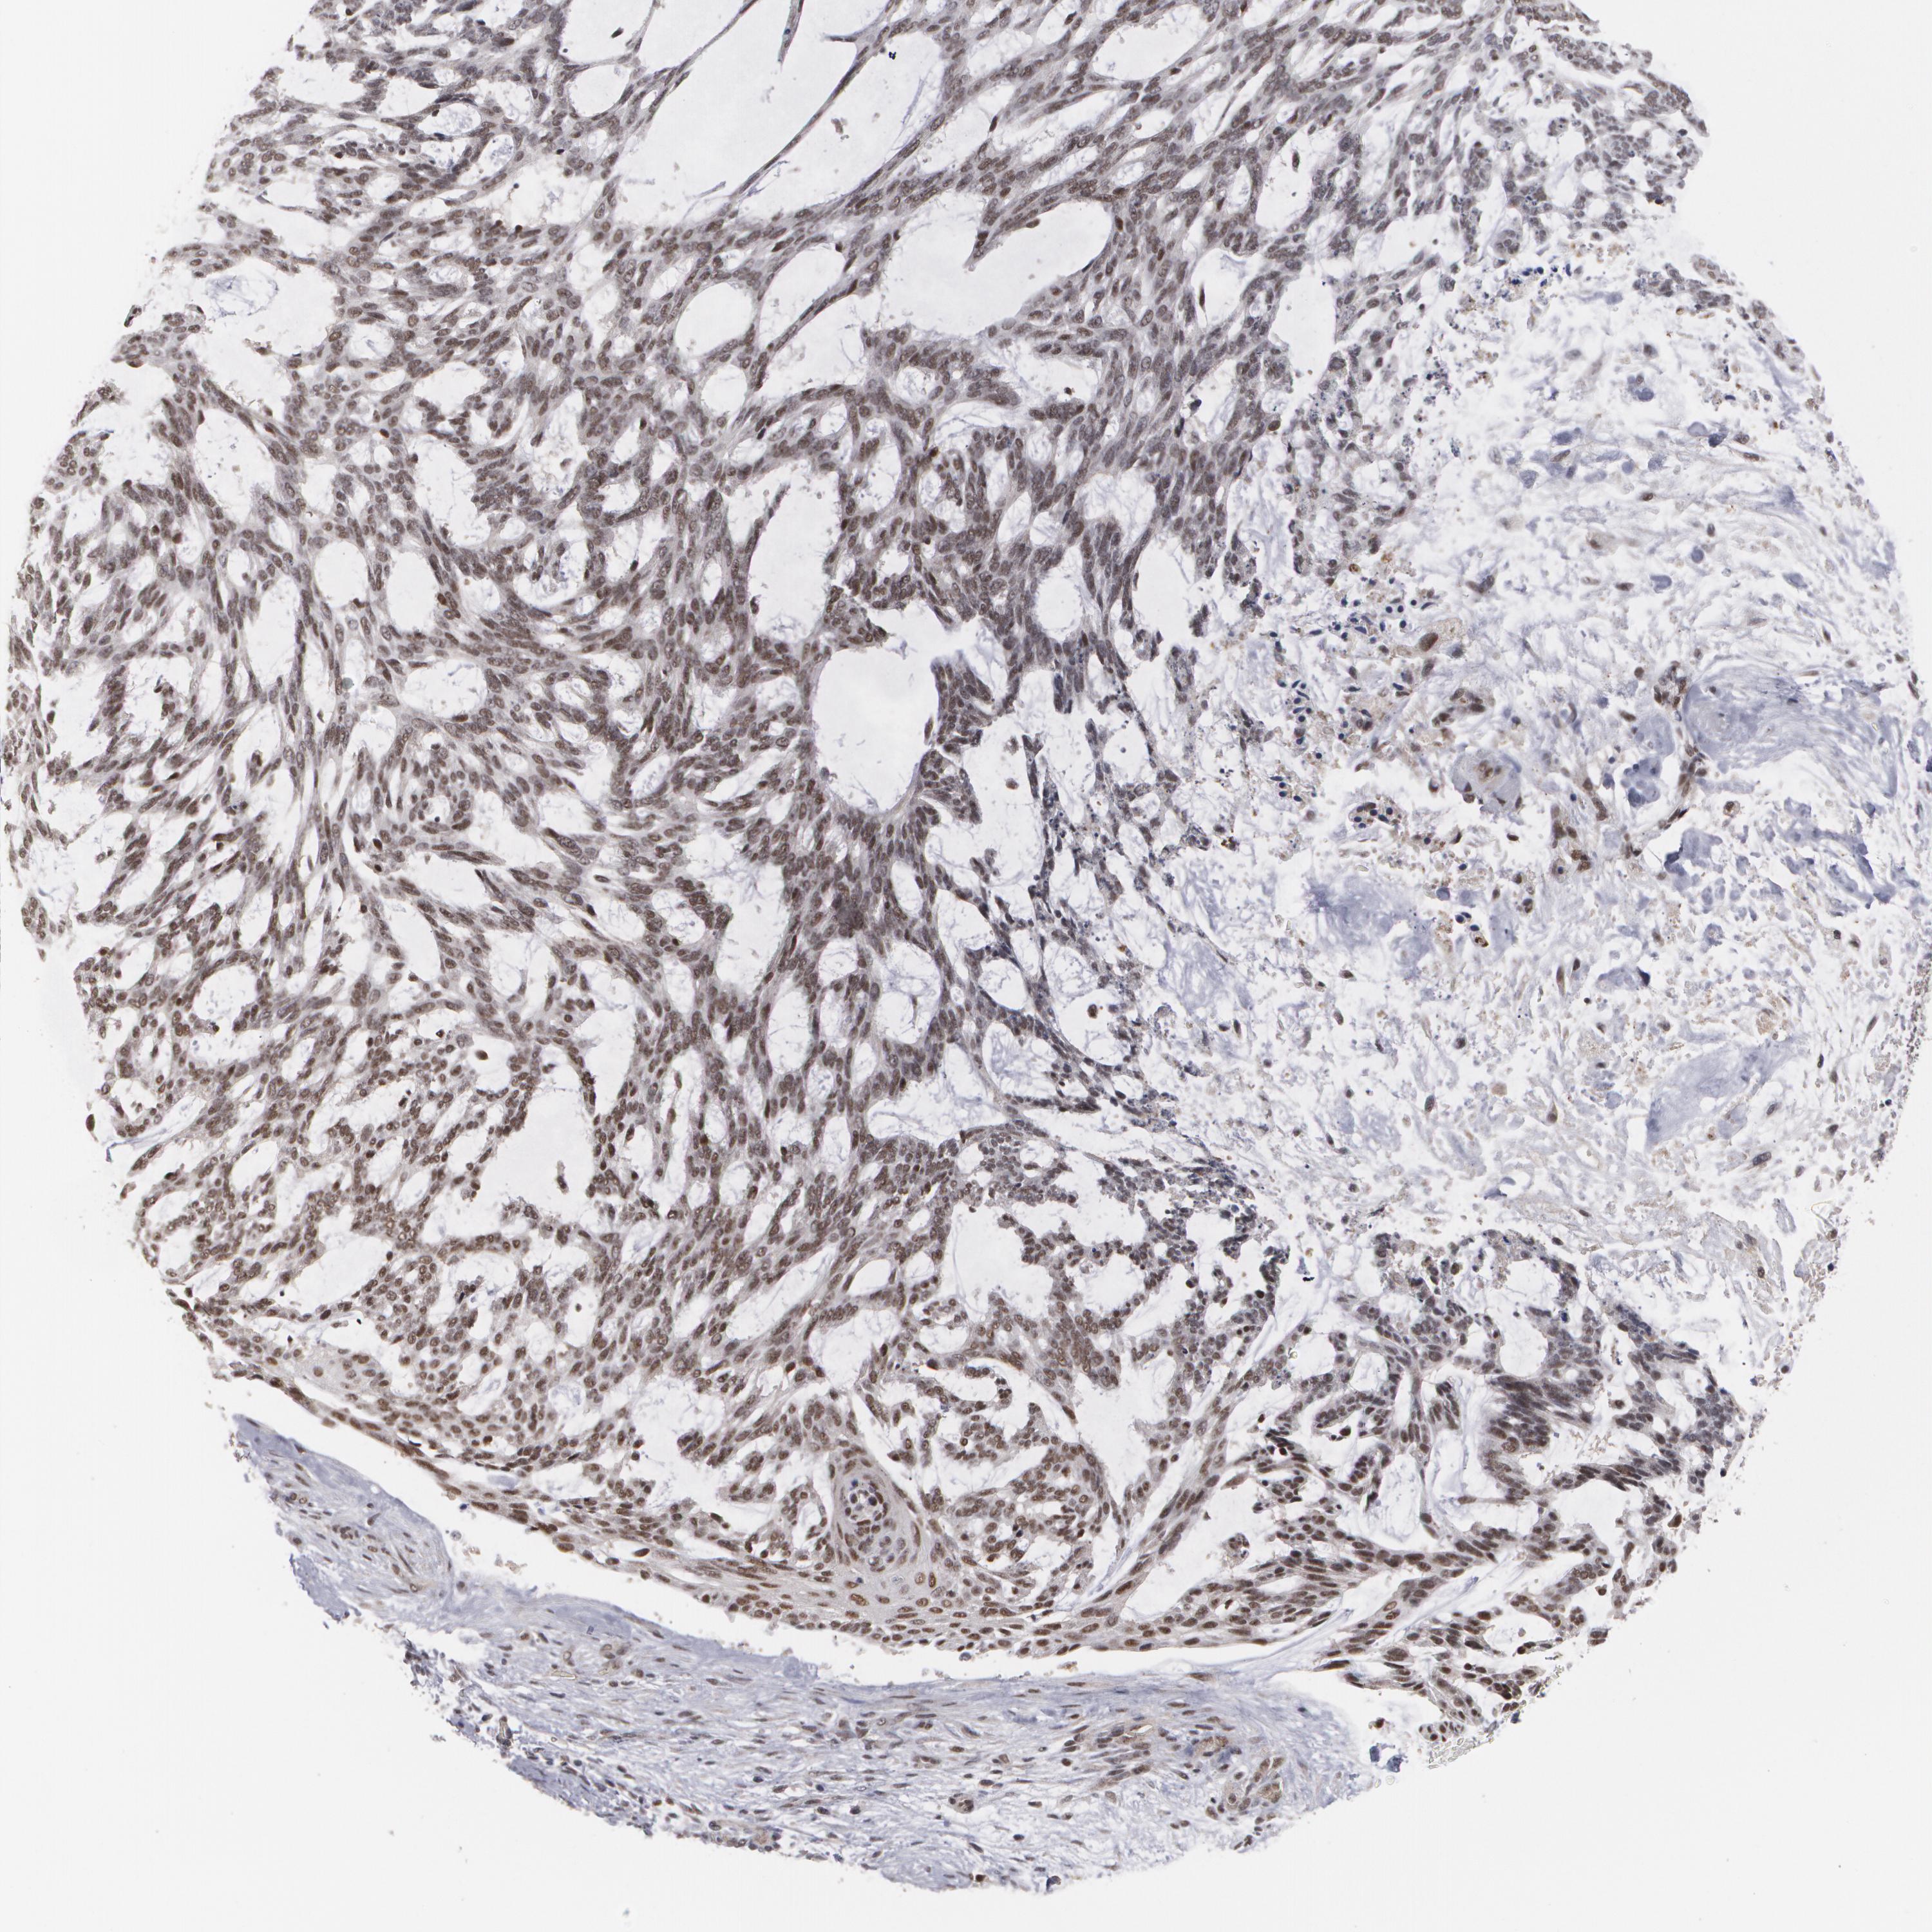

SKIN CANCER - Protein expressioni

A mouse-over function shows sample information and annotation data. Click on an image to view it in a full screen mode. Samples can be filtered based on level of antibody staining by selecting one or several of the following categories: high, medium, low and not detected. The assay and annotation is described here.

Antibody staining in the annotated cell types in the current human tissue is reported as not detected, low, medium, or high, based on conventional immunohistochemistry profiling in selected tissues. This score is based on the combination of the staining intensity and fraction of stained cells.

Each image is clickable and will lead to virtual microscopy that enables deeper exploration of all samples and also displays staining intensity scores, fraction scores and subcellular localization as well as patient and tissue information for each sample.

Antibody HPA001552

Antibody HPA001846

Staining

High

Intensity

Strong

Location

Nuclear

Squamous cell carcinoma, NOS